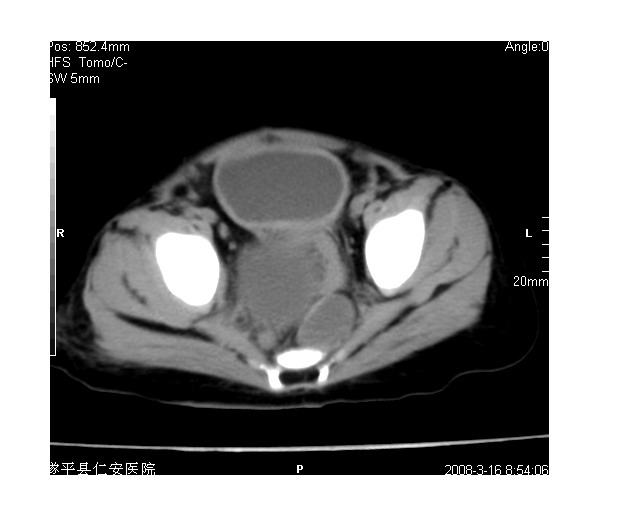

以下是引用lkc8963在2008-3-16 12:49:00的发言:[br]盆底巨大混杂密度肿块,富含多种组织成分包括脂肪/液体/软组织/钙化,边界清楚,向前压迫肠管及膀胱,向后突入骶尾部皮下脂肪层,首先考虑畸胎瘤,诊断时需要与脊柱裂/囊性淋巴管瘤等区别。